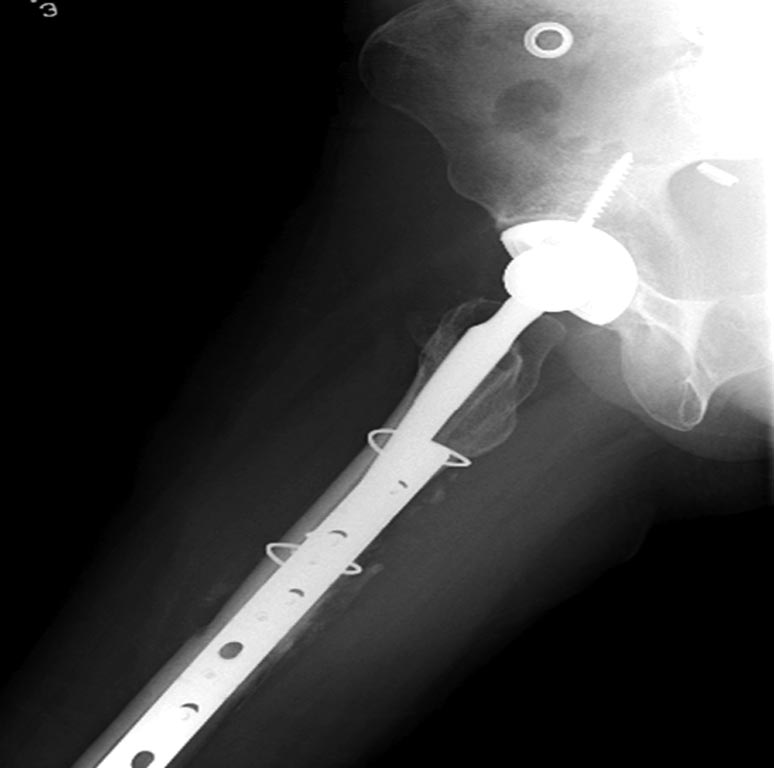

Из вариантов фиксации для проксимального и диафиза бедра выбрали пластину, а по поводу артропластики остается вопрос между тотальным или геми.

На всякий случай запланировали: короткий и длинный вариант ножки.

На 25 день с момента травмы операция на Jackson table с боковым обширным доступом. Удаление стержней с местной обработкой. В тазобедренном суставе удаление головки, на дне вертлужной впадины полная отслойка хряща. Вертлужный компонент с одним винтом и короткая ножка - Fitmore press fit stem. На второй день однократно доза радиации для профилактики гетеретопической оссификации. Послеоперационный период без температуры. Выписана. Нагрузку разрешили на левой стороне, а полная в 3 мес. Здесь снимки при амбулаторном наблюдении: послеоперационно, 2 мес, 3 мес и 6 мес. Нагрузка полная, отсутствует хромота, и нет жалоб.